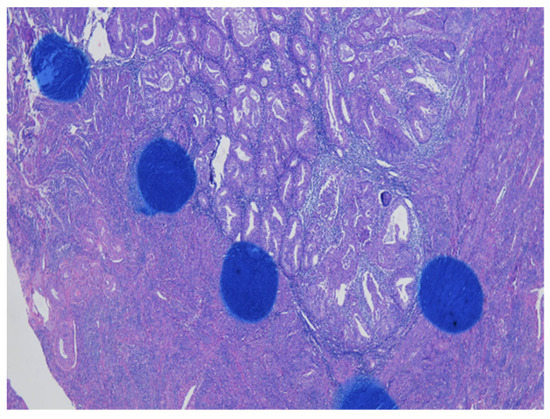

As shown in Figure 1 of EC at the uterine cornus, negative MI was found with an intact thin rim of stroma between the tumor–myometrium junction on the left side and with positive MI featuring an absence of stroma between the junction on the right side. A further higher power scope of the left side and right side of Figure 1 is shown in Figure 2 and Figure 3, respectively. Figure 2 demonstrated a thin rim of endometrial stroma between the tumor-myometrium junction (dark blue area: dark blue nuclei of stromal cells), and Figure 3 revealed the superficial early MI. MI determined by histopathology was the gold standard for comparison.

Figure 3.

The absence of stromal cells in between tumor and myometrium hints the superficial myometrial invasion (200× magnification).